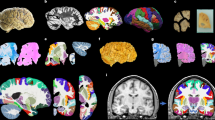

The hypothalamic atlas was generated by two raters (CN and JG) who manually labeled diencephalic and mesencephalic structures bilaterally using Display (Montreal Neurological Institute; http://www.bic.mni.mcgill.ca/software/Display/Display.html) (Fig. 2). To allow fine-grained labeling at great anatomical detail, segmentation was performed using the high-resolution, high-contrast template of enhanced anatomical detail (voxel size: 0.25 × 0.25 × 0.25 mm). The primary reference for the delineation of hypothalamic nuclei and surrounding structures was the Atlas of the human brain, fourth edition30. The Allen Brain Atlas (http://www.brain-map.org) served as a secondary reference31. Volumes were defined on T1-weighted (T1w) and T2-weighted (T2w) images. To facilitate the delineation of hypothalamic nuclei, structures with explicit tissue boundaries (i.e., clear contrast between regions) were labeled first. These included, among others, the anterior commissure, diagonal band of Broca, fornix, mammillothalamic tract, mammillary bodies, subthalamic nucleus, and substantia nigra (Fig. 3). White matter structures were included if they featured high-contrast borders (e.g. in close proximity to gray matter structures or cerebrospinal fluid). The borders of these anatomical landmarks were used to delineate implicit brain regions of low tissue contrast (Fig. 4). Structures that featured low contrast (e.g. medial forebrain bundle (mfb), fields of Forel, mammillotegmental tract) were not segmented. Of note, targeting of mfb has thus far relied on diffusion tensor imaging and tractographic identification; delineation of mfb based on structural MRI only is not possible32,33. Following labeling the dice similarity coefficient (DSC) was calculated for each label to determine the extent of inter-rater agreement. Labels associated with a DSC < 0.35 were reevaluated jointly and amended by both raters such that neuroanatomical differences were reduced to a minimum23,34,35. For the generation of the final diencephalic Atlas an OR logical was employed i.e. the label that was overall deemed more accurate was implemented in the final Atlas build.

2D representation of the hypothalamic atlas. Manually segmented hypothalamic and extrahypothalamic labels are overlaid on representative coronal T2-weighted (T2W) (two center left columns) and T1-weighted (T1W) (two center right columns) sections. Montreal Neurological Institute (MNI152 NLIN 2009b) coordinates and the distance from the midcommissural point (MCP) are shown. Reconstructions (left column) and histologic sections (right column) from the Atlas of the human brain were used to facilitate the delineation of hypothalamic and surrounding structures. ac, anterior commissure; AHA, anterior hypothalamic area; AN, arcuate nucleus; BNST, bed nucleus of stria terminalis; dB, diagonal band of Broca; DM, dorsomedial hypothalamic nucleus; DP, dorsal periventricular nucleus; fx, fornix; ithp, inferior thalamic peduncle; LH, lateral hypothalamus; MM, mammillary bodies; mt, mammillothalamic tract; nbm, nucleus basalis of Meynert; PA, paraventricular nucleus; PE, periventricular nucleus; PH, posterior hypothalamus; RN, red nucleus; SCh, suprachiasmatic nucleus; SN, substantia nigra; SO, supraoptic nucleus; STN, subthalamic nucleus; TM, tuberomammillary nucleus; VM, ventromedial nucleus; ZI, zona incerta. (Reproduced with permission from Mai JK, Paxinos G, Voss T (2016): Atlas of the Human Brain, 4th ed. San Diego: Elsevier Academic Press.

3D reconstruction featuring the topographic relationships between the hypothalamus and surrounding gray and white matter structures. (a) frontal view; (b) occipital view; (c) sagittal view of the hypothalamus (red) and surrounding structures (gray); (d) sagittal view of the medial surface of the right hypothalamus (red) and surrounding structures (gray). The anterior confines of the hypothalamus are comprised of the diagonal band of Broca (dB) and the anterior commissure (ac). The latter is directly neighbored by the bed nucleus of the stria terminalis (BNST) as well as the fornix (fx), which penetrates through the hypothalamus and terminates in the mammillary bodies (MM). Along with the mammillothalamic tract (mt), the fornix and mammillary bodies form part of the Papez circuit. The lateral boundary of the hypothalamus is formed by the subthalamic nucleus (STN), substantia nigra (SN), zona incerta (ZI), and red nucleus (RN). The lateral border is extended anteriorly by the inferior thalamic peduncle (ithp).

3D reconstruction of hypothalamic nuclei and their neuroanatomical relationships. (a) top view; (b) bottom view; (c) frontal view; (d) occipital view; (e) sagittal view depicting the outer surface of hypothalamic nuclei; (f) sagittal view depicting the inner surface of hypothalamic nuclei. Surrounding structures unrelated to the hypothalamus proper are transparent. AH, anterior hypothalamic area; AN, arcuate nucleus; DP, dorsal periventricular nucleus; DM, dorsomedial hypothalamic nucleus; LH, lateral hypothalamus; MPO, medial preoptic nucleus; PA, paraventricular nucleus; PE, periventricular nucleus; PH, posterior hypothalamus; SCh, suprachiasmatic nucleus; SO, supraoptic nucleus; TM, tuberomammillary nucleus; VM, ventromedial nucleus.

The contribution of the presented work are two data records featuring the minimal deformation, age- and population-averaged high-resolution templates and segmentations of the hypothalamic region. The high-resolution template comprises T1- and T2- weighted image files given in NIfTI-1 format. Both scans are available in ultra-high (voxel size: 0.25 × 0.25 × 0.25 mm) and high (voxel size: 0.5 × 0.5 × 0.5 mm) resolution. The second data record features the atlas of the hypothalamic region and contains a total of 25 subcortical gray and white matter regions per hemisphere. 13 of the 25 anatomical labels constitute hypothalamic nuclei (Fig. 5), while the remaining labels comprise adjacent structures such as fornix, inferior thalamic peduncle, nucleus basalis of Meynert, and bed nucleus of the stria terminalis. These structures were segmented owing to their clinical importance and employment as targets for DBS surgery. The high contrast and resolution of the template greatly facilitated hypothalamic segmentation and allowed visualization of tissue boundaries that would have otherwise not been delimitable (Fig. 2). Diencephalic structures are featured as full volume segmentations in 0.25- and 0.5-millimeter isotropic resolution. Furthermore, an archive featuring each respective structure in 0.25 mm resolution is supplied. A detailed description of the labeling criteria used to identify individual hypothalamic nuclei can be obtained from Sup. Table 1. Finally, we provide an archive of the three example datasets that were used for validation of the hypothalamic atlas. It features the volumes of tissue activated (VTAs) of two DBS patients as well as the delineation of a solitary metastasis in MNI152 NLIN 2009b space.

Spatial relationship between individual hypothalamic nuclei. Hypothalamic nuclei are depicted in a consolidated (top) and an expanded view (bottom) revealing the intrahypothalamic relationships across nuclei. AHA, anterior hypothalamic area; AN, arcuate nucleus; DP, dorsal periventricular nucleus; DM, dorsomedial hypothalamic nucleus; LH, lateral hypothalamus; MPO, medial preoptic nucleus; PA, paraventricular nucleus; PE, periventricular nucleus; PH, posterior hypothalamus; SCh, suprachiasmatic nucleus; SO, supraoptic nucleus; TM, tuberomammillary nucleus; VM, ventromedial nucleus.